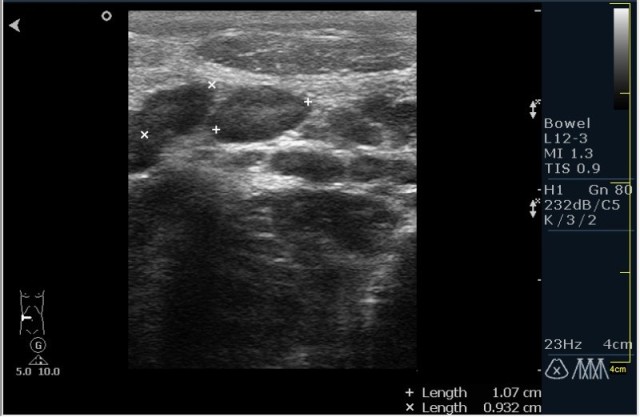

Ребёнок с болями в животе.

инвагинация! :!:

На представленных сонограммах определяется типичная "мишень" или "кокарда" (7ая и 8ая сонограмма сверху), которая при продольном сканировании превращается в "телескоп" (сонограммы 3 & 4). Все это указывет на инвагинацию кишечника (илео-цекальную). Причиной явилось лимфаденопатия брыжейки (которую вы указали). Увеличеные лимфоузлы вместе с инвагинатом хорошо различимы в просвете толстой кишки.

Уважаемые коллеги! Без сомнения имеет место илео-цекальная инвагинация.увеличенные овальные лимфоузлы, да еще такими гроздями характерны для мезаденита.Все зависит от развертывания клинической симптоматики.